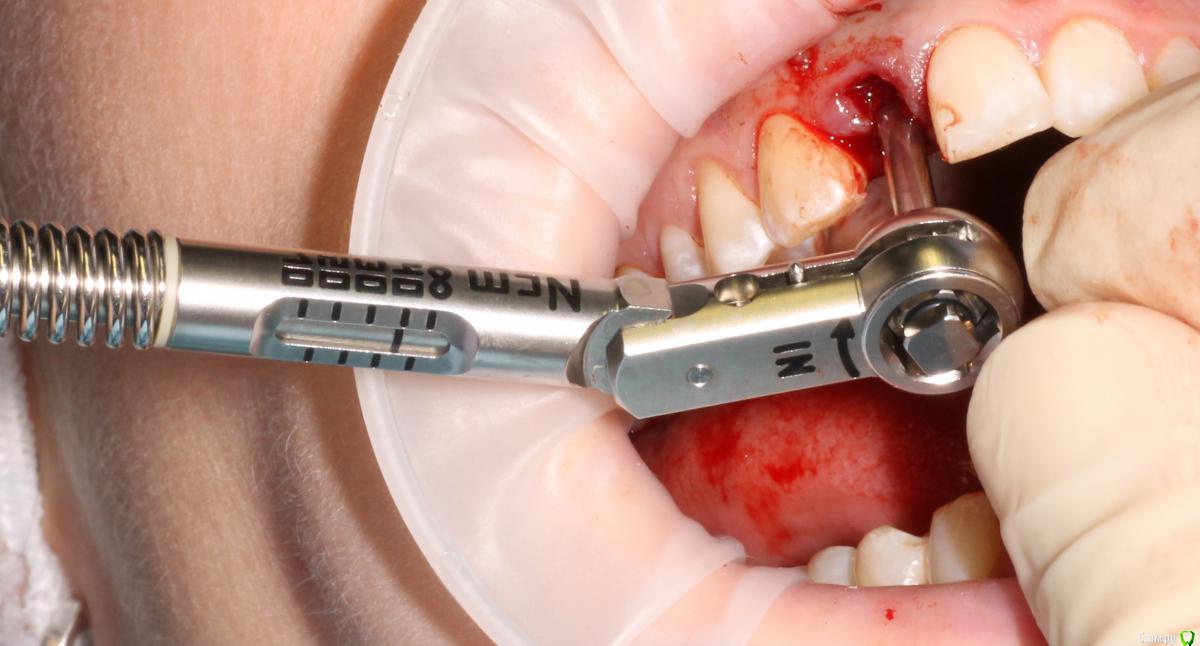

MenshikovDV Опубликовано 2 апреля, 2015 Поделиться Опубликовано 2 апреля, 2015 (изменено) Зуб 1.2 отлом коронковой части зуба, на период ожидания приема у хирурга и ортопеда (2 дня) приклеен к соседям. Вся процедура в одно посещение. Где-то часа два. Я ортопед, хирургия не моя, фото мои Изменено 2 апреля, 2015 пользователем MenshikovDV 19 Ссылка на комментарий

an_ver Опубликовано 2 апреля, 2015 Поделиться Опубликовано 2 апреля, 2015 SPI? В лунку что нибудь кидали во время установки? Ссылка на комментарий

Lolopop Опубликовано 3 апреля, 2015 Поделиться Опубликовано 3 апреля, 2015 альфабио?)))какой торк получили? Ссылка на комментарий

АнтонТЛТ Опубликовано 4 апреля, 2015 Поделиться Опубликовано 4 апреля, 2015 Судя по фото Alpha bio SPI, торк около 40 Ссылка на комментарий

MenshikovDV Опубликовано 5 апреля, 2015 Автор Поделиться Опубликовано 5 апреля, 2015 торк намного больше 40 Ссылка на комментарий